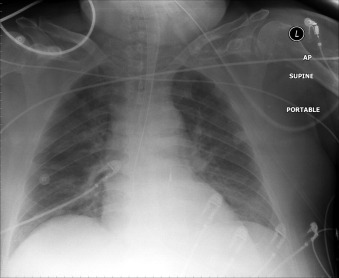

The tip of an intra-aortic balloon (which is highly visible because of its metallic marker) should be at least 4 cm below the “knuckle” of the aorta (i.e., below the left subclavian artery). The balloon appears as a cylindrical lucency if the radiographic exposure happened to be while it was inflated in diastole. Widening or haziness of the aorta suggests aortic dissection as a complication of the catheter. Incorrect insertion into the inferior vena cava is suggested by the shadow of the catheter lying to the right of the patient’s vertebral column.